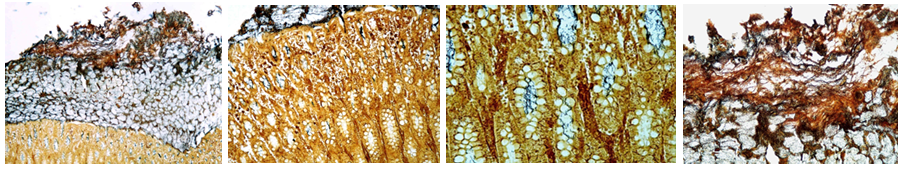

Adenoma et adenocarcinoma sebaceum

Description: 2 sections on slide. Adenoma is smaller, adenocarcinoma larger. Epidermis has relatively normal structure, in some places it intrudes into the tumor with acinar structure. It consists of many gland clusters lined by narrow interstitial tissue. Tumor is relatively large, light cells with vacuolated foamy cytoplasm and large, light nuclei. In some nuclei there are necrotic changes. In adenocarcinoma proliferated glandular cells are more basophilic and pathological mitosis can be observed in nuclei. Alveolar centers undergo regressive changes (dystrophy, necrosis)

Etiology: Exact causes are unknown, but can have a genetic and environmental component

Pathogenesis: Adenoma is a benign epithelial tumor occurring in various glands (circumanal, sebaceous, mammary) and also adrenal and thyroid glands. Lesions can be difficult to differentiate from nodular hyperplasia. A common group is the basal cell group, deriving from basal layer of squamous epithelium and can differentiate into tumors of any adnexa of skin. Adenocarcinoma is a malignant gland-forming neoplasm. They can grow in papillary form and in retention of secretion (cystic hyperplasia). Tumors can be well or poorly differentiated.